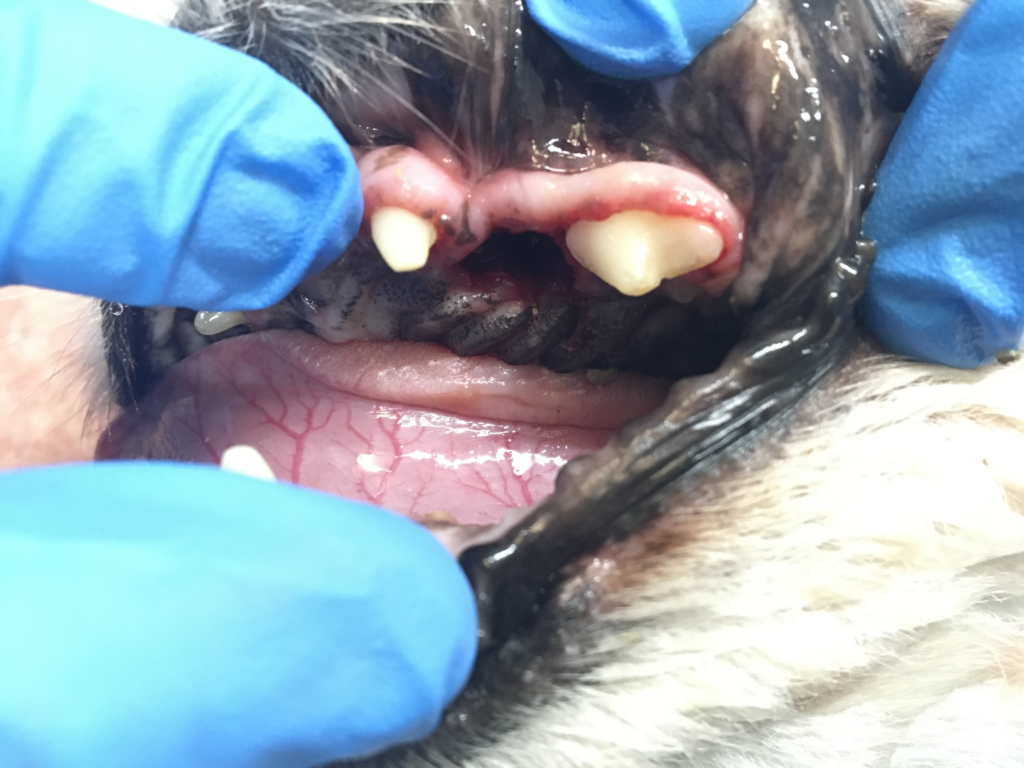

今回の症例は、くしゃみを主訴に来院されました。歯周病以外の疾患の除外と、歯周病箇所の場所の特定のため、CT検査を行いました。

左の上顎第1〜3前臼歯が鼻腔とつながっていることがわかったため、歯科処置にて、抜歯とフラップ形成を行いました。